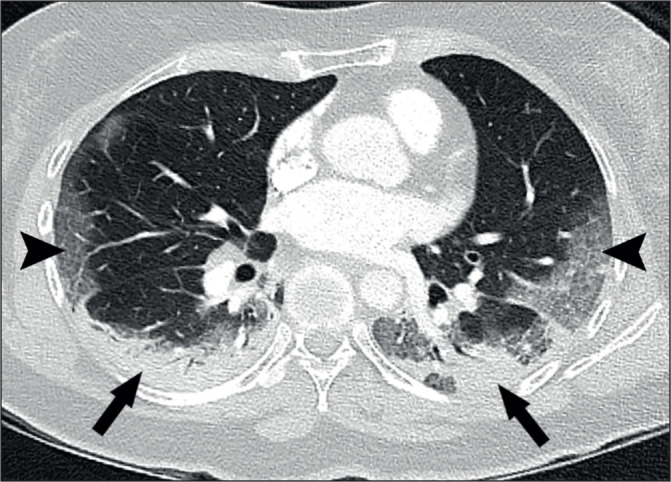

Results: Parenchymal lung damage was found in all subjects. However, airways inflammation was present in only 23% (9) and limited to small areas. Notably, vascular abnormalities were dominant and characterised by dilated peripheral pulmonary vessels supplying areas of lung damage in a gravity-dependent distribution bilaterally in 95% (38), basally in 90% (36), peripherally in 92.5% (37), and posteriorly in 90% (36). Macrothrombosis was demonstrated in 23% (7) of CTPAs. Wedge-shaped peripheral lung damage, resembling areas of pulmonary vascular congestion, were distinct in 53% (21) with or without visible macrothrombosis. Pleural effusions were seen in 28% (11). Notably, lung opacification distribution in 98% of the plain radiographs matched distribution on CT (39).